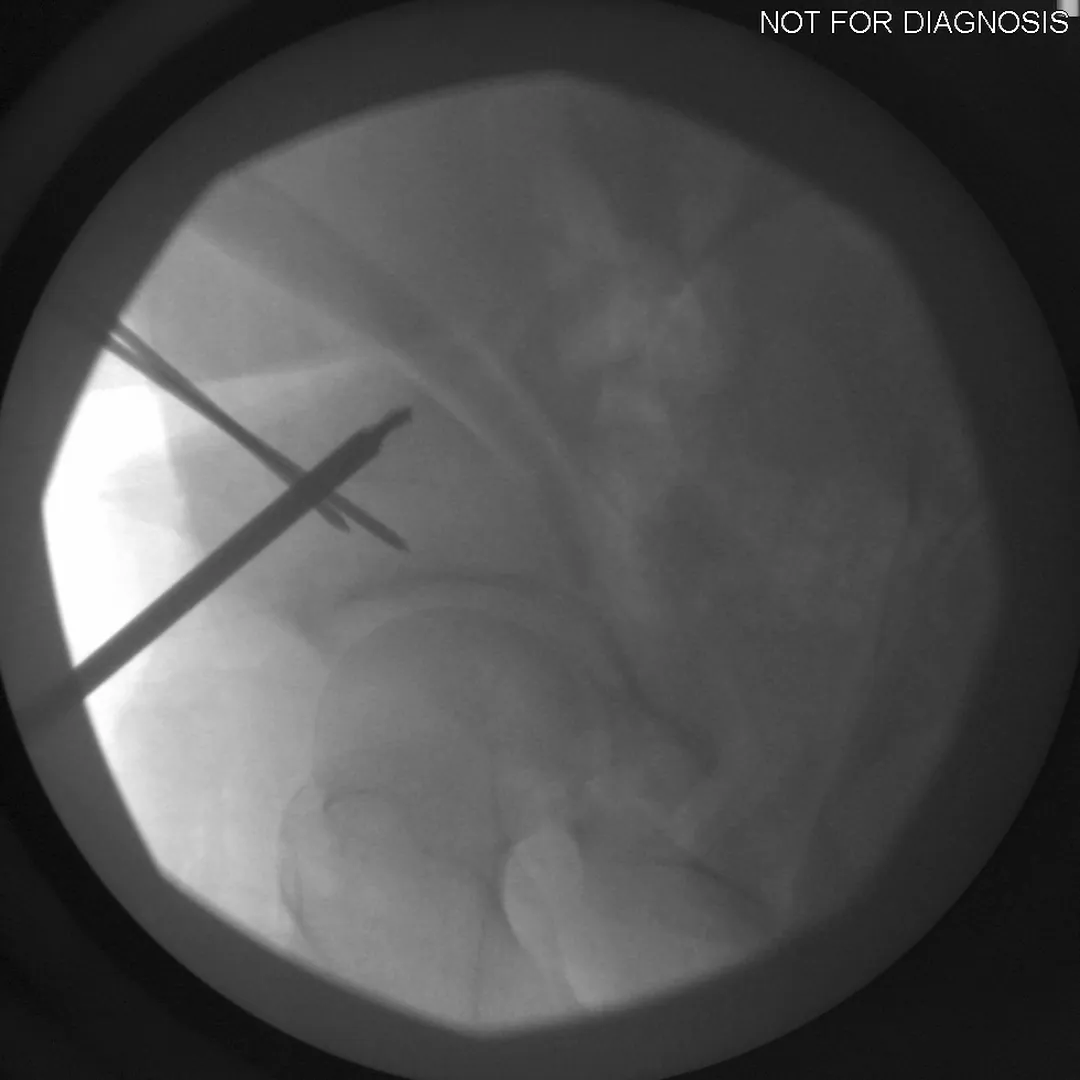

The Surgery

• PAO surgery typically takes 2-4 hours

• It is performed under general anesthesia

• Several controlled bone cuts are made around the hip socket

• The socket is repositioned and fixed with screws

• The hip joint itself is preserved